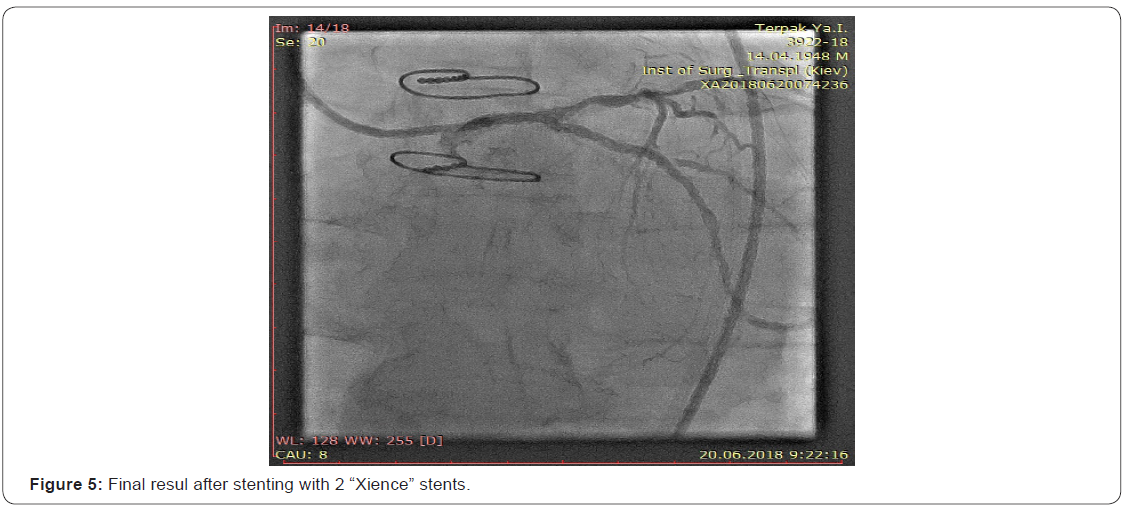

After the stenting of the CX with 2x stent “Xience” flow was completely restored (Figure 5). At control coronaroangiography the competitive blood flow in the distal artery through a stenotic venous bypass still existed. We refrained from bypass embolisation in view of its «jumping character» and the fear of occlusion of the blood flow to the DB of the LCA.